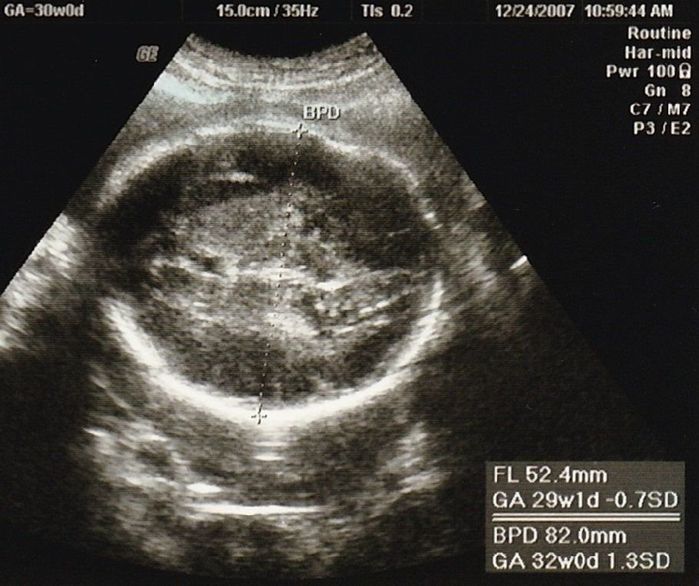

妊娠30週目のエコー写真

赤ちゃんの大きさは標準の真ん中あたり。胎盤の位置や羊水の量も正常、母子ともに問題はありませんでした。